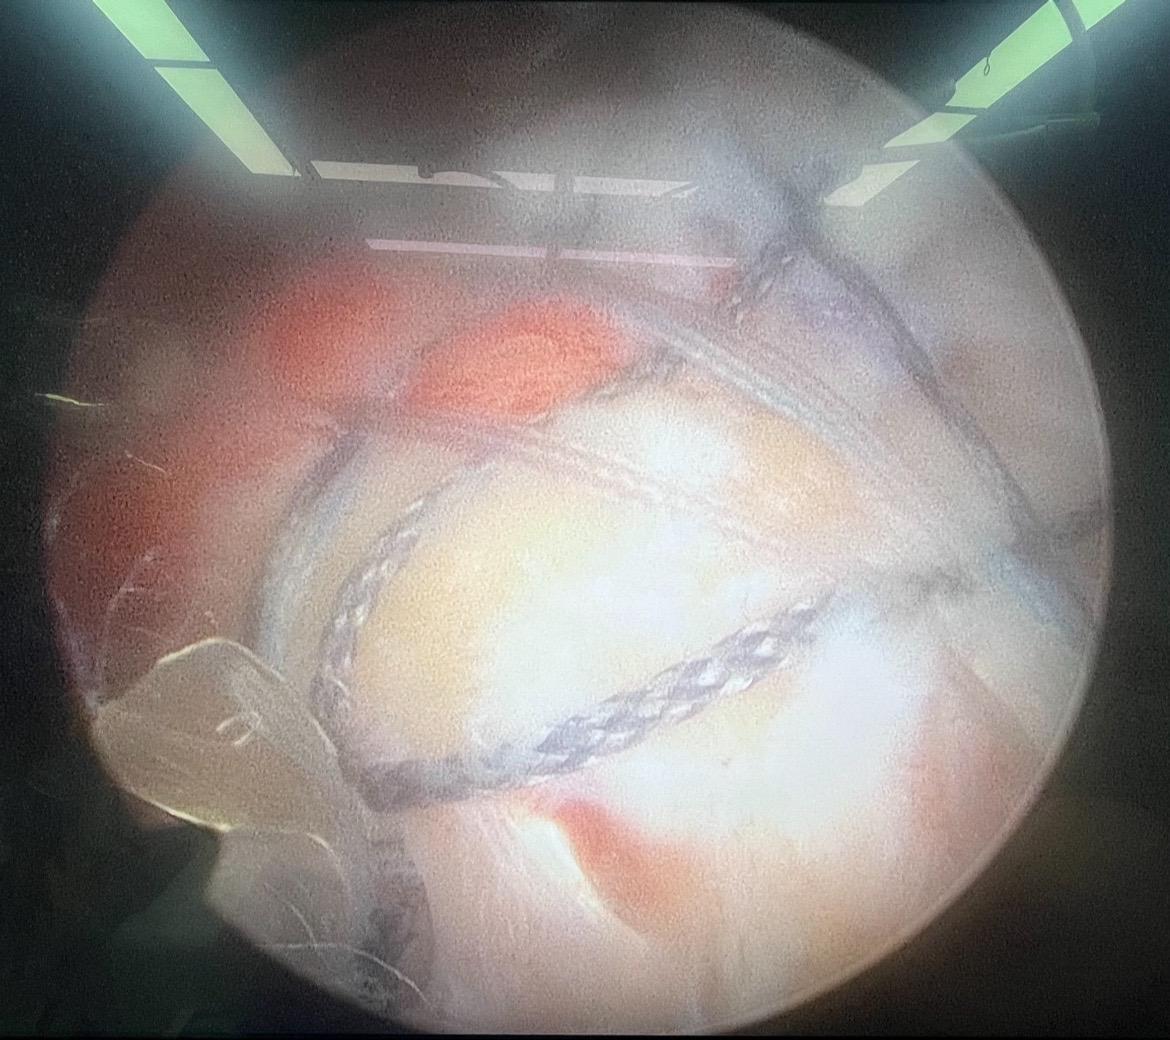

巨大肩袖撕裂修复。每一次置钉过线,每一次钳抓,每一次调整,都凝聚了我们的专业和努力,手术成功,患者安好,这是对术者最大的奖赏 肩袖撕裂 巨大肩袖撕裂 关节镜手术 关节镜微创手术